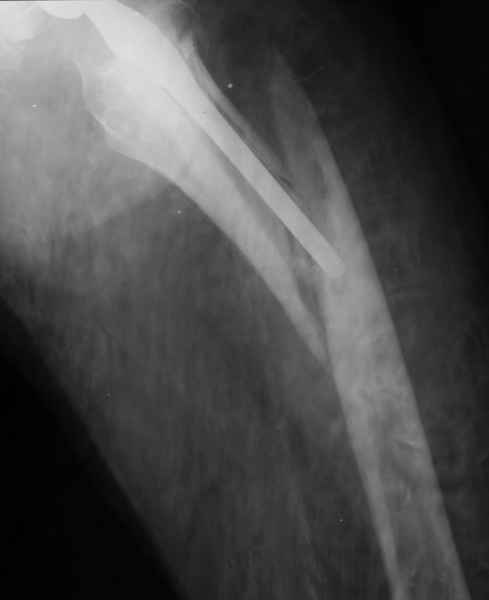

Хочется показать два подобных случая, П-ка Зубарева 72 лет и п-т Гладковский 80 лет. Сразу принимаю замечание, что это были ножки цементной фиксации, просто под руками не было бесцементника.